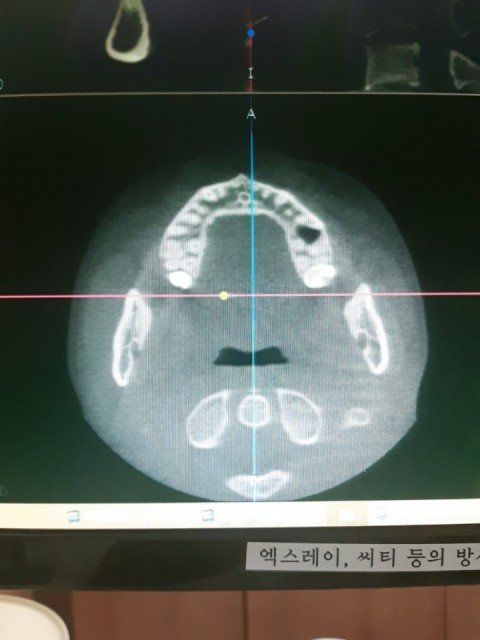

입안 잇몸밑에 하악쪽 뼈있는곳이 자까 벗겨지고 까지집니다. 2년넘게 증상이 나아지지 않고 혀로 문질러 보면 느낌도 까칠하고 무슨 지렁이 같은게 붙어 있는거마냥 그런 느낌이 납니다 손가락으로 긁어서 보면 지우개 가루같이 흰색으로 되어있는 이물질들이 나옵니다. 치과에 가보니 충치 치주질환 등 그런것들은 아니라고 (인천에 있는 대학병원)큰병원에 가보라고 해서 혹시나 악성이 아닐까 걱정도 하고 ct도 찍어보았으나 아무런 문제가 없다고 하는데... 증상은 계속돼고... 이유가 뭘까요? 참고로 제가 후두염 식도염 있고 그리고 위가 좀 안좋은것같은데 연관성이 있을까요?

(인천에 위치한)대학병원에서 촬영한 것입니다.